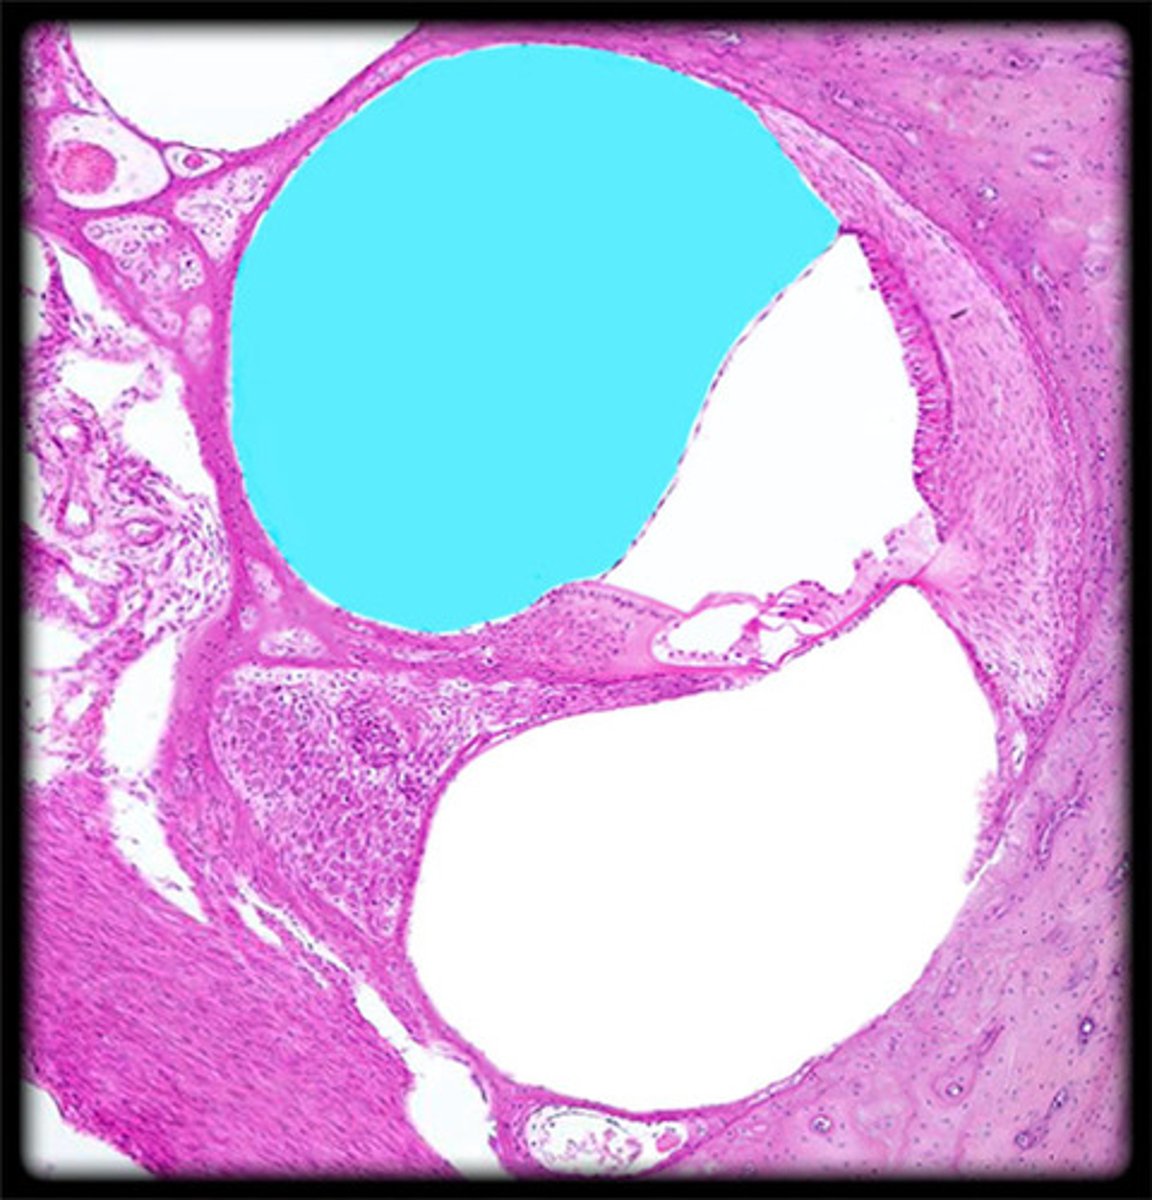

cochlea histology

scala vestibuli

contains perilymph

scala media

contains endolymph

scala tympani